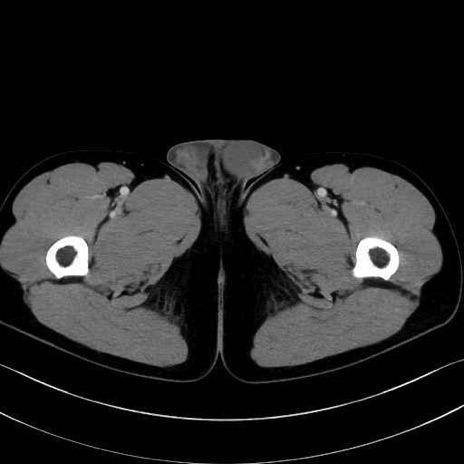

2. 腸腰筋群と骨盤底筋

大腰筋 (Psoas major)

腸骨筋 (Iliacus)